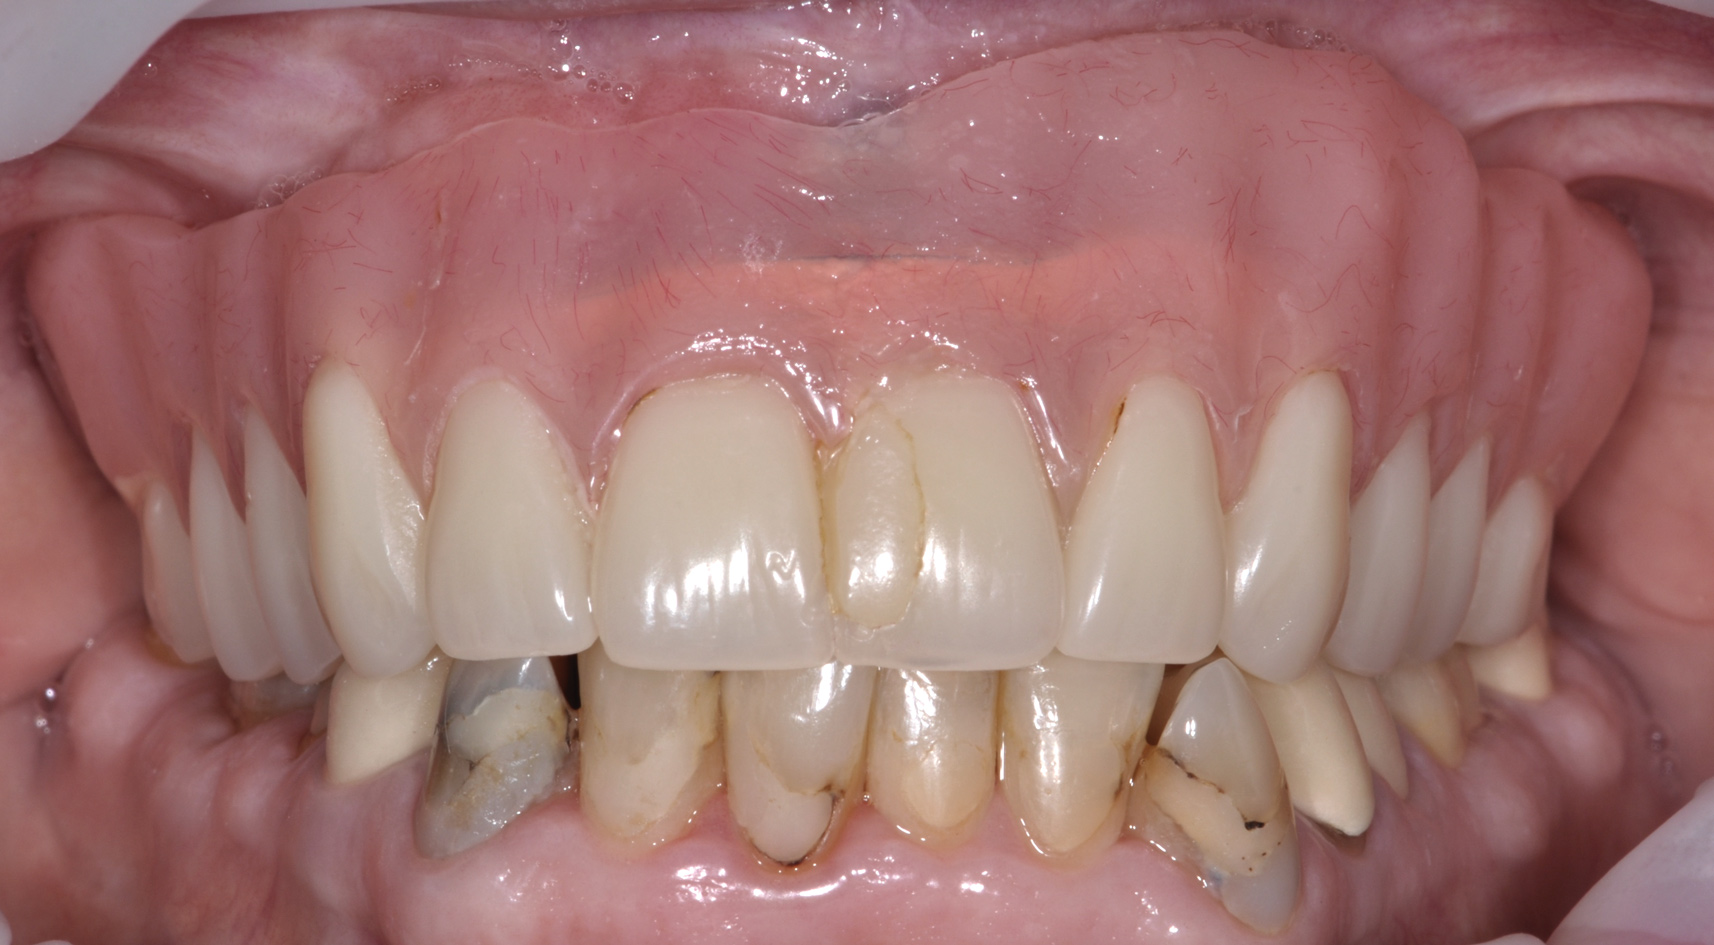

The main objective of peri-implant mucositis treatment is the resolution of inflammation.18 Oral healthcare providers should employ a two-pronged approach in the treatment of peri-implant mucositis. First, they should consider the patient's ability to perform adequate oral hygiene around the implant prosthesisthis includes assessing the patient's accessibility to the area in the mouthand prescribe appropriate aids in biofilm removal (Figure 1 and Figure 2). Second, the clinician should institute mechanical therapy and an appropriate peri-implant maintenance regimen consisting of further evaluation and treatment, if needed.

The clinician should review and reinforce with the patient the patient-administered oral hygiene efforts. Use of an intraoral stain to demonstrate inadequate plaque control has been shown to be effective in patient motivation.19 Nonsurgical peri-implant treatment should consist of mechanical removal of the bacterial biofilms and elimination or control of all local plaque retentive factors. Curettes, sonic and ultrasonic instruments, as well as air polishing with glycine powder are all effective methods of biofilm removal.20 The use of local antibacterials and local or systemic antibiotics appear to have minimal benefit.21 Once the treatment of peri-implant mucositis has been rendered, it is very important that the oral healthcare provider evaluate the response to therapy (Figure 3 and Figure 4). If initial therapy fails to resolve the peri-implant inflammation, it may be beneficial to assess the marginal fit and design of the implant prosthesis with regard to patient access, as well as the possible presence of cement remnants.

Fig 3. Nonsurgical peri-implant treatment was performed, and the existing prosthesis was modified to enable access for patient-administered oral hygiene.

Figure 3

Fig 4. Four weeks after treatment, the patient presented with healthy peri-implant tissues.

Figure 4